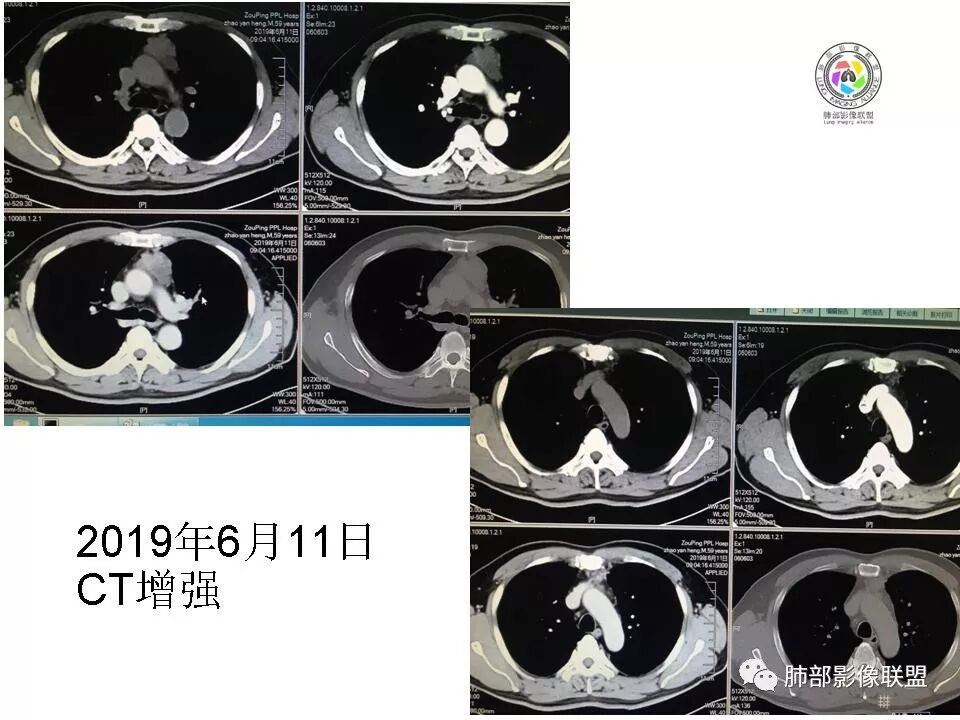

胸腺瘤(B2–C)型。中年男性,体检前上纵隔近奇静脉水平不规则呈生姜样占位,密度不均,延迟强化,进行性增大。

胸腺区实性占位,呈分叶状,病灶近一年间明显增大,增强扫描中度强化,病灶与周围组织界限模糊,考虑恶性,胸腺癌(鳞癌)。

胸腺区占位,较前明显增大,病灶边缘不规整,病灶明显强化,考虑侵袭性胸腺瘤

胸腺区实性占位,呈分叶状,病灶近一年间明显增大,增强扫描中度强化,病灶与周围组织界限模糊,考虑恶性,没有胸水,胸腺癌可能。

前中纵隔肿块灶,轮廓不规则,边缘不清,强化较均匀明显强化,考虑侵袭性胸腺瘤可能

前纵膈占位,与前比较增大,边缘不规整,强化,考虑胸腺瘤,

前纵膈占位,前后明显增大,病灶边缘不规整,分界不清,病灶明显强化,考虑侵袭性胸腺瘤

研究了半天,纵隔是我短板,[擦汗]中老年男性,病灶边界不清,边缘有低密度灶,有强化,延迟强化,考虑胸腺癌。

2015年小,2019年增强,不规则强化不均匀。

48-60-70,28-30-24,不规则渐进性强化,密度不均。

诊断:侵袭性胸腺瘤

前纵隔占位,分叶明显,随访明显增大,不均匀强化,考虑侵袭性胸腺瘤。

前纵隔胸腺区占位,边缘不规则,可见分叶,增强不均匀强化,考虑胸腺瘤。

前纵膈胸腺区占位,病灶边缘不规整,分叶,病灶明显强化,中央有坏死,考虑胸腺鳞癌,鉴别侵袭性胸腺瘤。

前纵膈胸腺区占位,分叶,病灶明显强化,侵袭性胸腺瘤?

分叶状,结节感,边界模糊,强化,考虑恶性病变,胸腺癌可能性大

老年男性,15年胸腺区小结节,19年明显增大,边缘不整,明显分叶,增强后不均匀强化,考虑内部坏死,周围脂肪间隙模糊,考虑恶性,胸腺癌?

前纵隔占位,病灶边缘不规整,分叶,病灶强化明显,中央有坏死,考虑恶性,胸腺癌?

前纵隔肿块较前明显进展,边缘出现大片囊变,实性部分明显强化,内见沙粒样钙化,考虑恶性肿瘤,倾向胸腺鳞癌或神经内分泌癌

前纵隔占位,可见分叶,部分坏死,边缘不规整,考虑胸腺癌凝睦:

前纵隔占位,不规则,分叶,密度不均匀,周围有小淋巴结,考虑胸腺癌

前纵隔占位,分叶状,病灶较前增大,增强扫描中度强化,周围脂肪间隙模糊,考虑胸腺癌。

定位前纵膈,边缘清楚,形态不规则,有分叶,右侧肺门淋巴结肿大,有强化,考虑恶性 胸腺癌可能。

4年增大,分叶,有淋巴结增大,多见于胸腺癌。

前纵隔占位,分叶状,病灶较前增大,增强扫描中度强化,周围淋巴结,考虑恶性,胸腺癌可能性大。